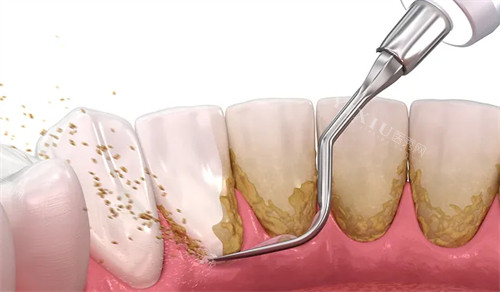

洗牙:基础洁牙 99 元起 / 次,超声波洁牙 + 抛光 150 元起 / 次。